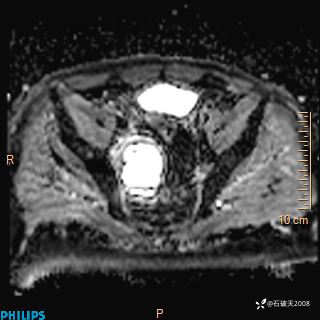

2023年3月份MRI影像

增强轴位